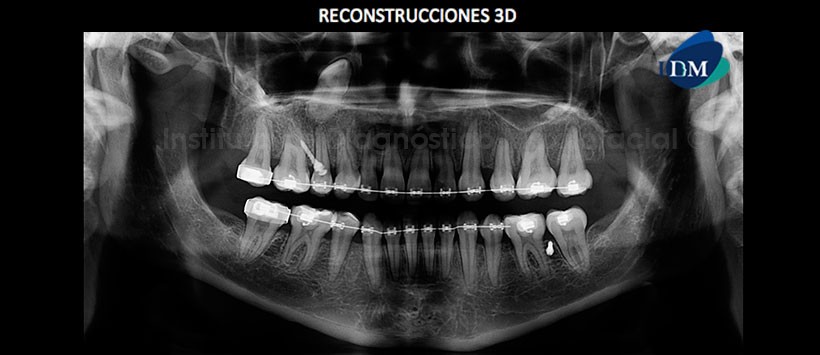

En las reconstrucciones 3D (Figura 4 y Figura 5) notamos que dicha pieza no repercute en las estructuras dentarias adyacentes. Además de que mediante la opción “diente segmentado” que nos brinda el software Romexis, podemos aislar la pieza en evaluación, ver su ubicación en relaciona los tejidos blandos (Figura 6) y también en relación al escaneo facial. (Figura 7)